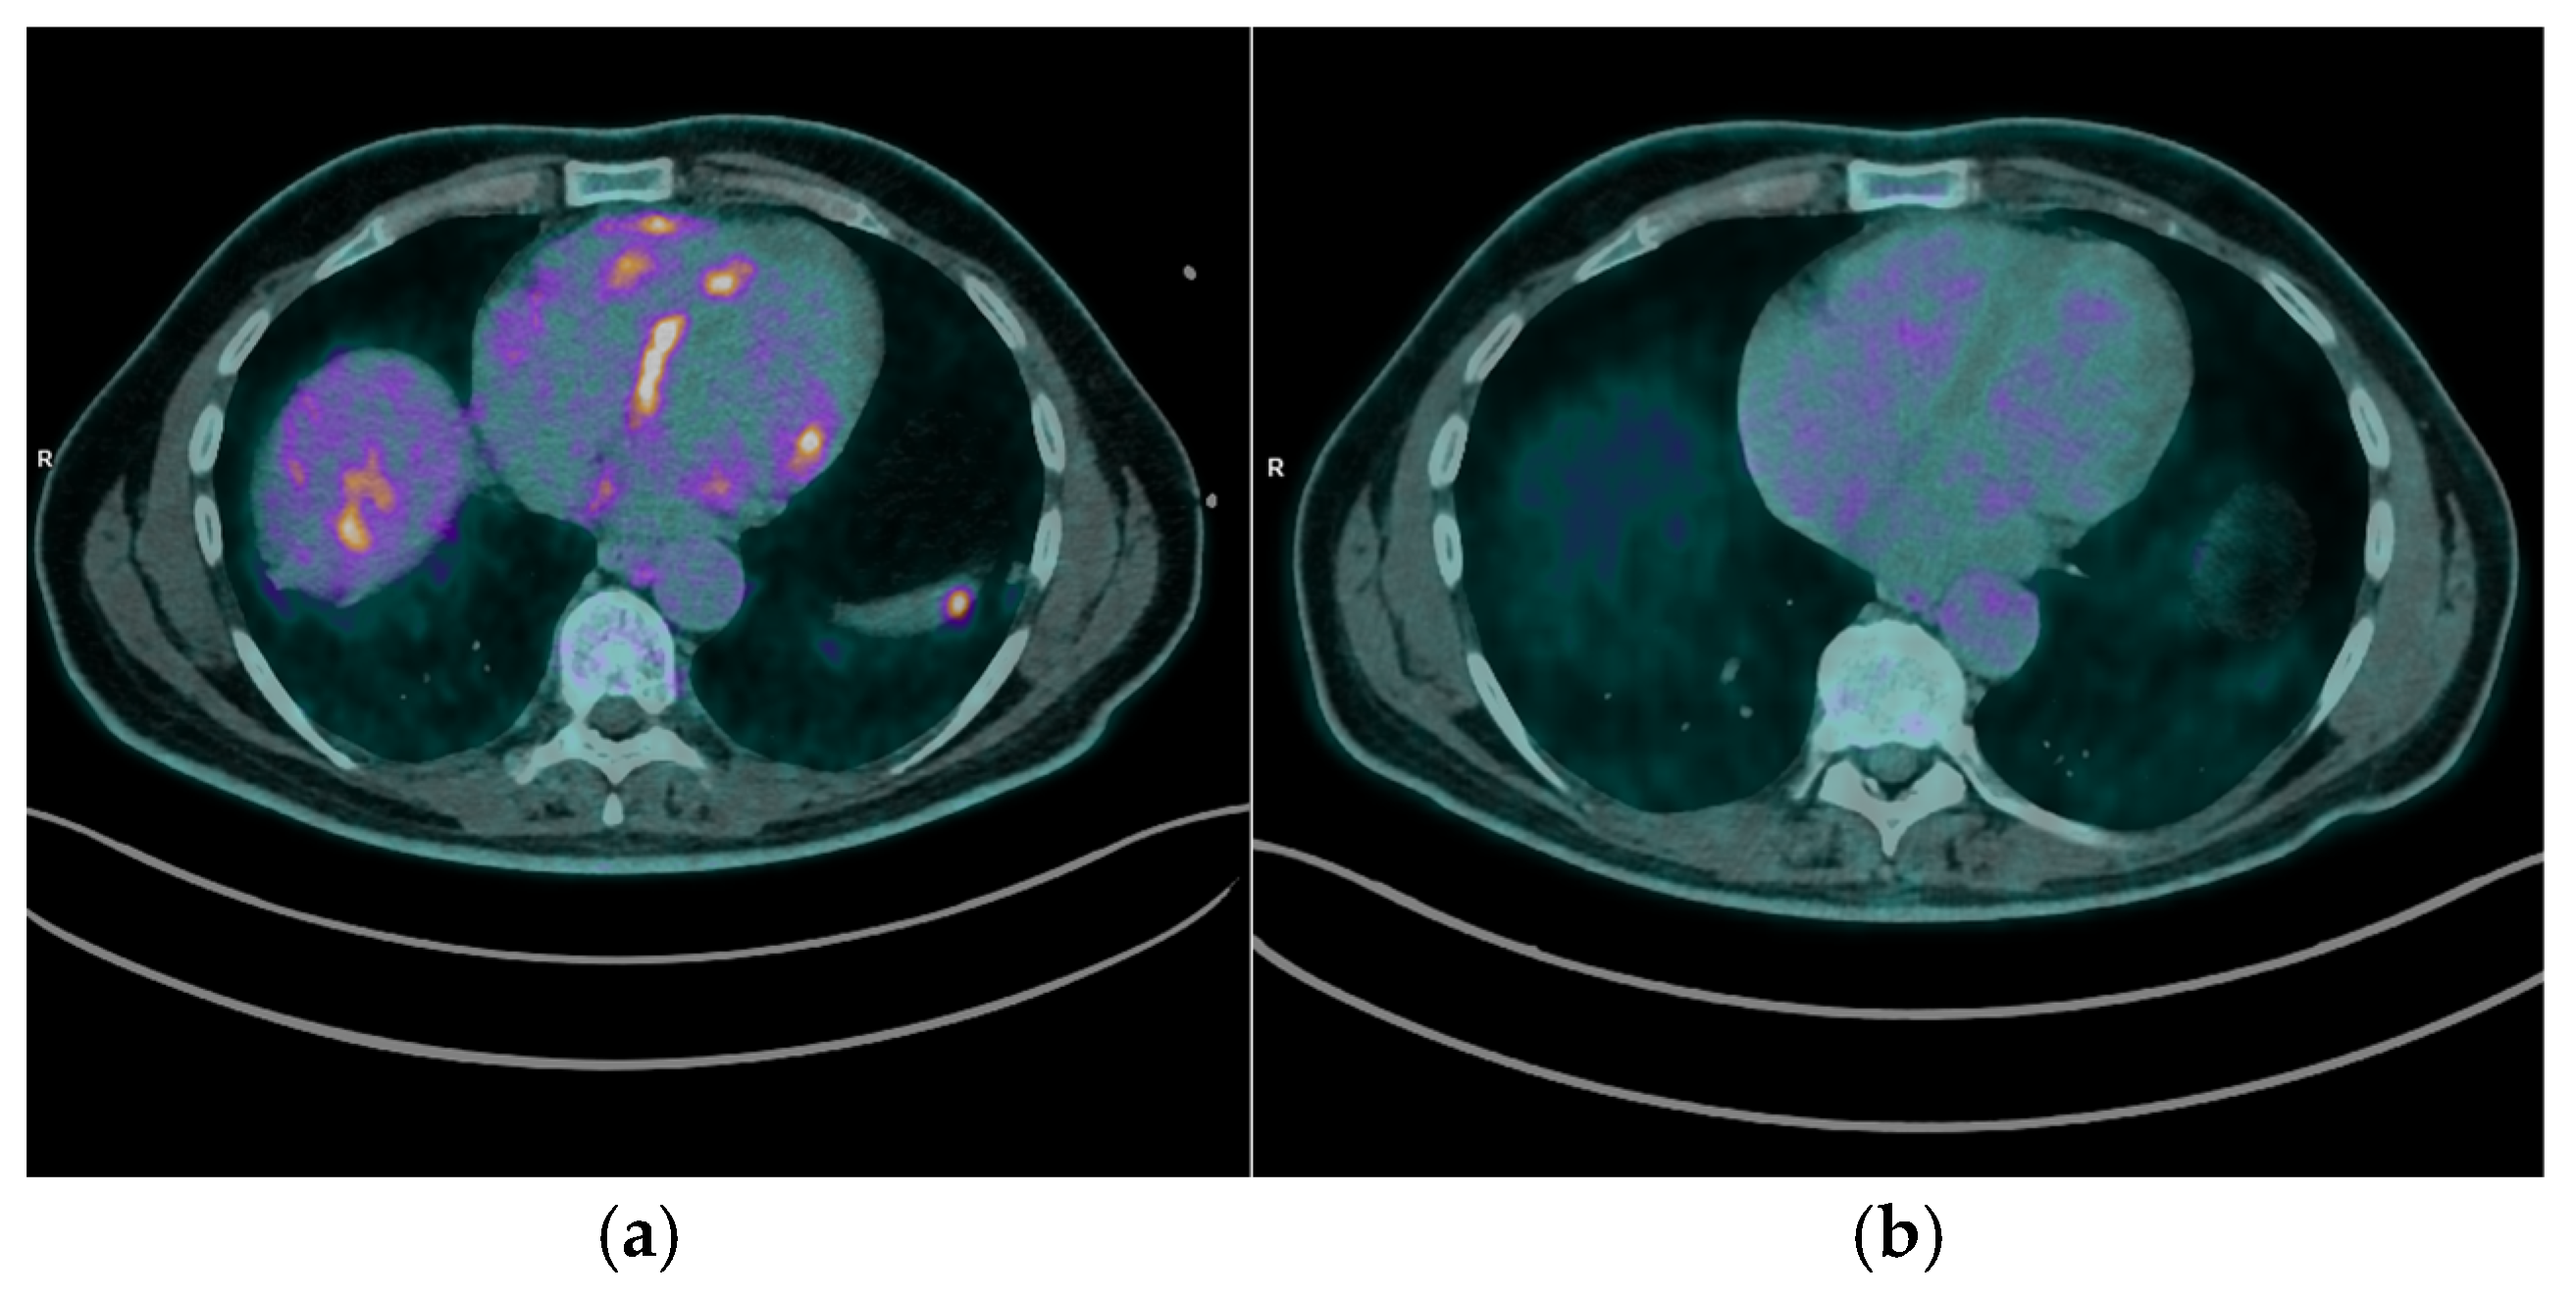

- The integration of perfusion imaging with 13N-NH3 PET/CT enhances the diagnostic and prognostic value of PET/CT. By distinguishing areas of perfusion defects (indicative of fibrosis) from regions of increased FDG uptake (active inflammation), clinicians can fully characterize the spectrum of disease, from isolated inflammation to fibrosis, and overlapping pathology, for comprehensive disease evaluation, prognosis, and guiding tailored therapeutic strategies [9].

- Cardiac magnetic resonance (CMR) imaging is the first-line advanced diagnostic test for CS; however, it was not feasible for all patients and sometimes produced inconclusive results, further illustrating the diagnostic gap that PET/CT can address. In this regard, our findings confirm that FDG PET/CT is highly sensitive for detecting active myocardial inflammation, as demonstrated by the characteristic uptake patterns observed.

- Moreover, our findings reinforce the utility of PET/CT in guiding individualized treatment strategies. By offering a non-invasive assessment of myocardial inflammatory activity, PET/CT allows clinicians to tailor immunosuppressive therapy based on objective evidence of disease activity or remission. This approach facilitates the adjustment of immunosuppressive regimens, such as corticosteroids and steroid-sparing agents, while minimizing unnecessary exposure to medication side effects, thereby improving patient safety and quality of life [13]. Serial PET/CT imaging enhances disease monitoring by enabling quantitative and qualitative assessments of therapeutic response. In our cohort, follow-up PET/CT scans confirmed a complete metabolic response in most patients (77.8%), supporting decisions to taper immunosuppressive therapy in selected cases (25%). Conversely, persistent or recurrent FDG uptake necessitated continued or intensified treatment (75%), underscoring the role of PET/CT in dynamic, patient-centered clinical management.